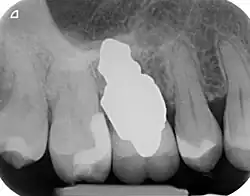

RAIs are custom made to perfectly fit the tooth socket of a specific patient immediately after tooth extraction. Therefore every implant is unique. As an optimised root-form it is much more than a simple 1:1 replica of a tooth. Since it exactly fills the gap left after the tooth is extracted, surgery is rarely needed. The implant can be produced from a copy of the extracted tooth, an impression of the tooth socket, or from a CT scan or CBCT scan.[7] The advantage of a CBCT scan is that the implant can be produced before extraction. With the former methods, it takes one or two days to fabricate an implant.

- Obtain the 3D form of the tooth to be replaced. This is done either through careful tooth extraction and scanning of the root, taking an impression of the tooth socket, or a pre-op CBCT scan. The root analogue implant is produced using modern CAD/CAM technology, based on the principle of differentiated osseointegration;

- Placement of the root analogue implant by tapping it in. In general, no surgery is necessary. In particular, no sinus lift or invasive surgery is ever necessary. The implant is placed immediately if it has been produced beforehand from a CBCT scan, or the next day if root has to be scanned or an impression of the socket is used. A protective splint is fitted to protect the implant during the healing period.

- Natural form: a custom milled anatomic implant replicates the natural form of a tooth, so it simply fits into the tooth socket. Like the original tooth, a root analogue implant can have single- and multi-rooted forms.